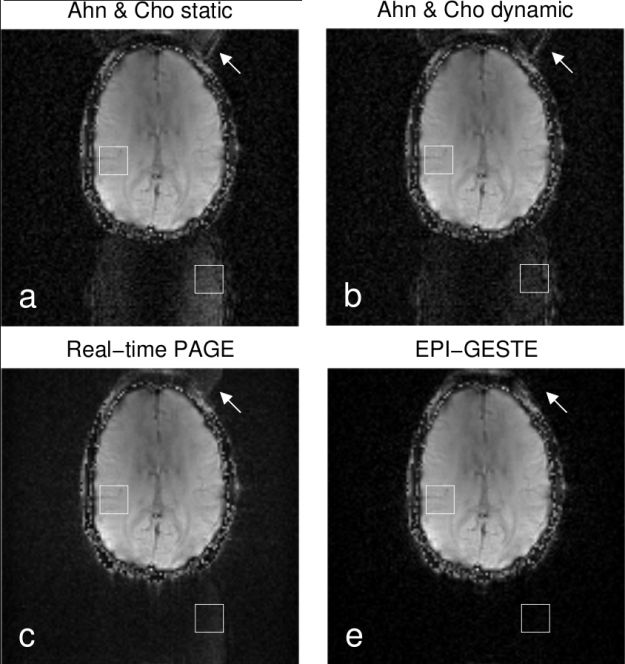

- Images reconstructed using EPI-GESTE show very low Nyquist ghosts, much lower than the product reconstruction code

- We have a new method for self-referenced EPI ghost correction (EPI-GESTE)